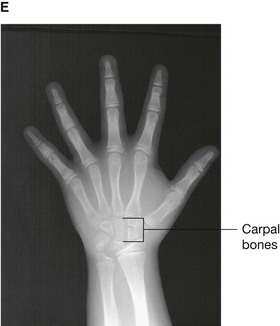

Up until the age of skeletal maturity, bony growth and development follows a typically predictable ordered state, which can be measured through either ultrasound, plain radiographs, or MRI scanning. Typically, the nondominant (left hand) is radiographed and is compared to a series of standard radiographs. From these images the bone age can be determined (Fig. 1.13).

image image image image image

Fig. 1.13 A developmental series of radiographs showing the progressive ossification of carpal (wrist) bones from 3(A) to 10(E) years of age.

In certain disease states, such as malnutrition and hypothyroidism, bony maturity may be slow. If the skeletal bone age is significantly reduced from the patient’s true age, treatment may be required.

In the healthy individual the bone age accurately represents the true age of the patient. This is important in determining the true age of the subject. This may also have medicolegal importance.